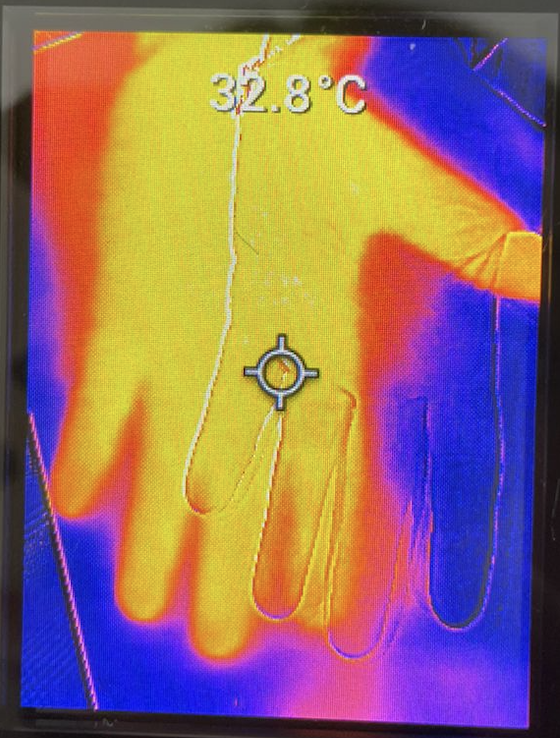

Dorso de la mano de un paciente con Disautonomia

Palma de la mano de un paciente con disautonomía